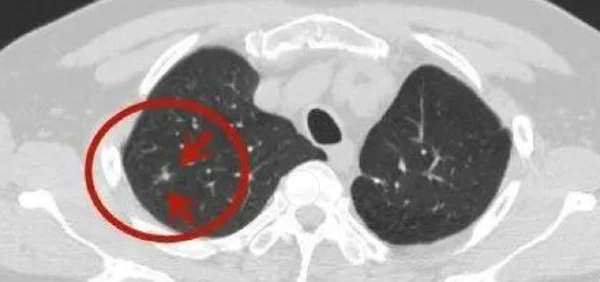

从病理生理学角度,右肺上叶结节可以是实性结节或亚实性结节。实性结节一般意味着更大的恶性风险,而亚实性结节则可能代表一种较慢的生长模式。影像学检查常用于判定结节的性质和特征,如结节的形态、密度和内含物等。

影像学检查是发现和初步评估肺部结节的主要手段。通过胸部CT扫描,可以清晰显示结节的大小、形态、位置及内部结构,有助于初步判断结节的性质。对于高风险的结节,可能需要进一步的PET-CT检查来评估代谢活性。